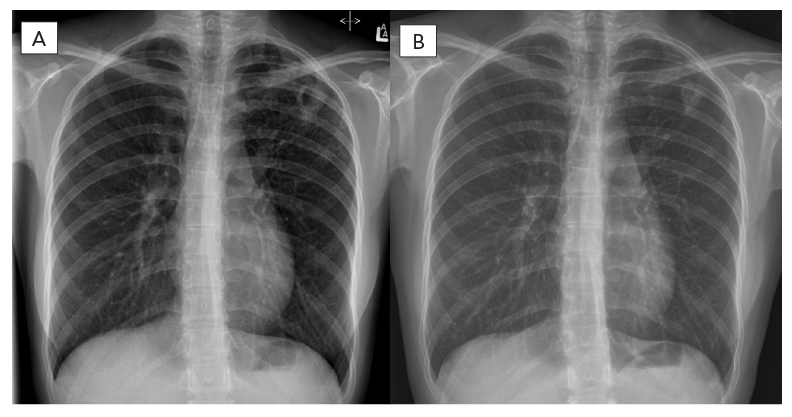

En mars 2021, une jeune femme de 18 ans a été aiguillée vers un programme provincial de lutte contre la tuberculose, avec des antécédents de toux depuis cinq mois et des sueurs nocturnes depuis plusieurs semaines. Une radiographie thoracique a révélé une cavitation du lobe supérieur gauche (figure 1). Les échantillons d'expectorations ont démontré la présence de bacilles résistants à l'acide par frottis, ce qui a été confirmé comme complexe de Mycobacterium tuberculosis par un essai de réaction en chaîne par polymérase ciblant les gènes IS6110 et mpt64. La patiente est née en Chine et avait déménagé au Canada trois ans avant le diagnostic de tuberculose. Elle n'avait ni exposition connue à la tuberculose, ni traitement, elle ne fumait pas et elle ne prenait pas de médicaments. Les enquêtes de référence étaient négatives pour le virus de l'immunodéficience humaine, l'hépatite B/C et le diabète.

Figure 1 - Équivalent textuel

La radiographie du côté gauche montre une lésion cavitaire à paroi épaisse dans le coin supérieur du poumon gauche avant le traitement et la radiographie de droite montre une amélioration lors du suivi six mois après la fin du traitement.

Un mois après l'hospitalisation et l'optimisation du traitement, tous les symptômes de la tuberculose avaient disparu et les tests sur les expectorations ainsi que les cultures étaient négatifs. La série d'imageries thoracique pendant les suivis montrait une amélioration. En novembre 2021, le traitement par les antibiotiques BPaL a été interrompu. Plus de six mois après le traitement, la patiente n'avait aucun symptôme, les cultures d'expectorations étaient négatives et l'imagerie thoracique montrait une guérison (figure 2 et figure 3).